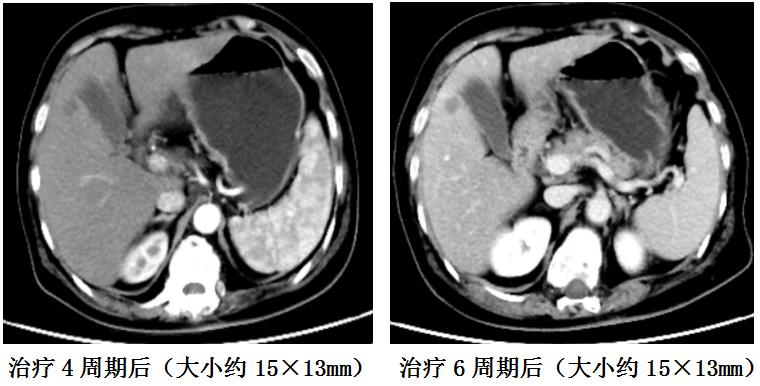

后因疫情影响及就诊于我科,科内会诊讨论患者病历资料、充分评估病情后继续免疫治疗联合化疗3周期。2022-06-28胸腹部CT提示肝脏转移灶无明显缩小,遂调整化疗方案治疗2周期,同步继续免疫治疗。2022-08-17复查胸部腹CT提示肝S5结节1.5x1.3cm无明显变化。无痛胃镜示胃角、窦小弯瘢痕样改变。病理活检示慢性萎缩性胃炎。2022-08-20至今行免疫维持治疗,既往有“2型糖尿病”病史10余年,治疗期间化疗反应轻微,未出现免疫治疗药物相关不良反应,目前患者一般情况良好。